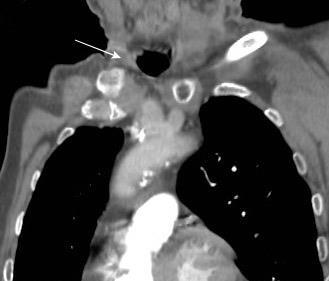

Conglomerado adenopático axila derecha. Linfoma de Hodgkin.

Santamarina MG et al. Multidetector CT for Evaluation of the Extrapleural Space. Radiographics 2017